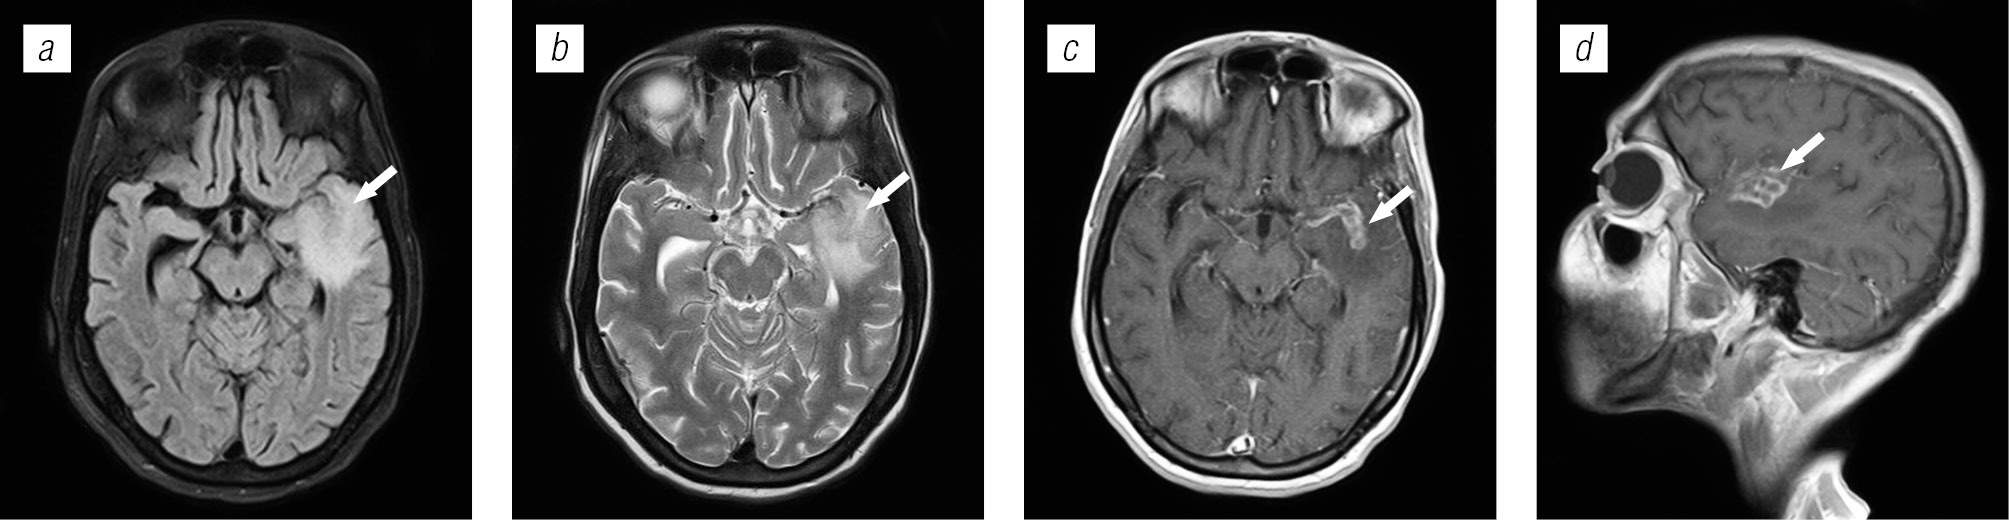

Структура оппортунистических и вторичных заболеваний была представлена токсоплазмозом головного мозга (18,3 %), герпесвирусными поражениями (12,2 %), прогрессирующей мультифокальной лейкоэнцефалопатией (10,24 %), нейроинфекцией неуточненной этиологии (12,2 %), криптококкозом (4,39 %), туберкулезом (2,44 %), лимфомой головного мозга (2,44 %), МАК-инфекцией (0,24 %).

Поражение головного мозга у ВИЧ-инфицированных больных во многом характеризуется синхронностью (микст-инфекция в 8,52 %) и мультифакторностью поражения.